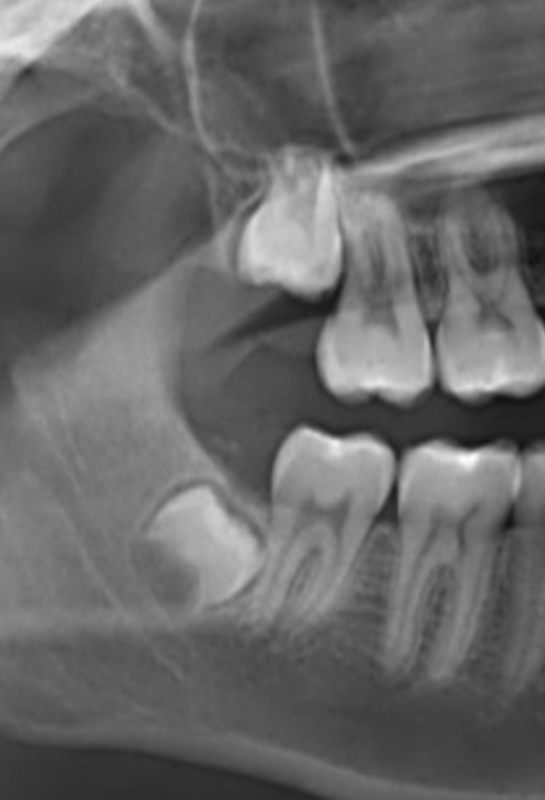

Wisdom teeth extraction

Third molars or wisdom teeth usually erupt in the late teens or early 20s. Depending on the size of the patient’s mouth and the position of the mouth, these teeth can cause discomfort to the patient such as pain, inflammation, and infection. If treatment is not given in a timely manner, then bone loss, periodontal problems and the loss of adjacent teeth may occur.In many cases the third molars partially from the socket or in sideways causing food impaction, irritation of the gingival tissues. Because of their position, it is hard to keep them clean and the tooth may start developing carious lesions or it can be the cause for carious lesions on neighboring teeth. In some cases, the teeth may not case any harm and if the patient is able to keep the clean with proper hygiene and regular cleanings then the teeth can be left untouched. If you fell that your wisdom teeth may need to be removed contact us to evaluate if removal of wisdom teeth is right for you.